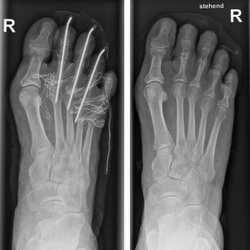

|  |

Behandlung eines einfachen Falls des Hallux valgus | Behandlung eines ausgeprägten Falls des Hallux valgus |